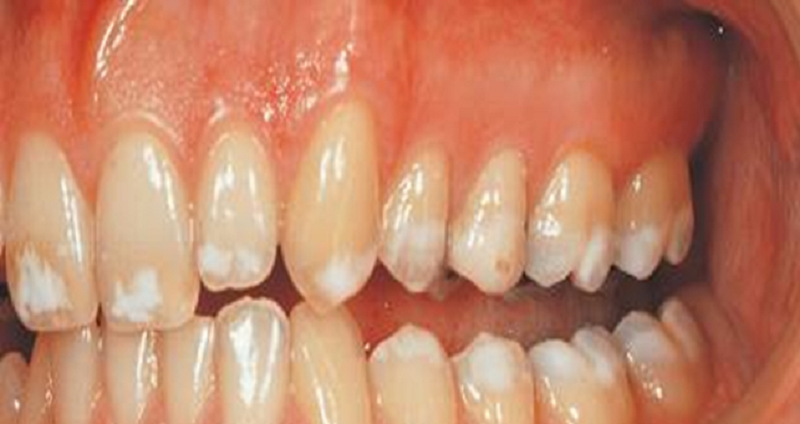

{"name":"Oral Path ID Chapter 6-9", "url":"https://www.quiz-maker.com/QPREVIEW","txt":"This condition is linked with Keratinosis of the palms of the hands & the soles of the feet. Individuals with this condition are likely to experience tooth mobility and premature tooth loss., This Term is used to describe The Appearance of type III (hypomaturation) Amelogenesis Imperfecta, Radiographs of a person with this condition appear to have a multilocular or “soap bubble” appearance","img":"https://www.quiz-maker.com/3012/CDN/92-4508546/final-pic-1.png?sz=1200"}